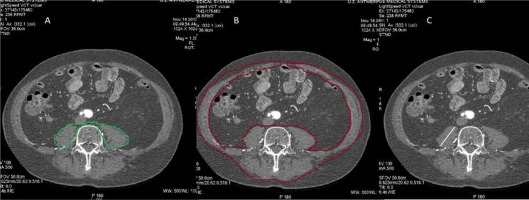

FIGURE 3

The different definitions used to assess sarcopenia. Panel A and B show the contouring of the region of interest to determine the psoas muscle area (PMA) (green colour) and the skeletal mass area (SMI) (red colour), respectively. Panel C demonstrates the measurement of the transverse psoas muscle thickness (TPMT) (white line)